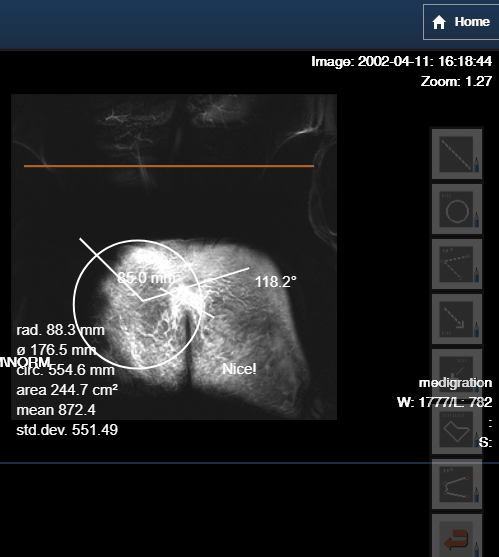

Bei Messungen in Projektionsradiographiebildern werden entsprechende Benutzerhinweise angezeigt.